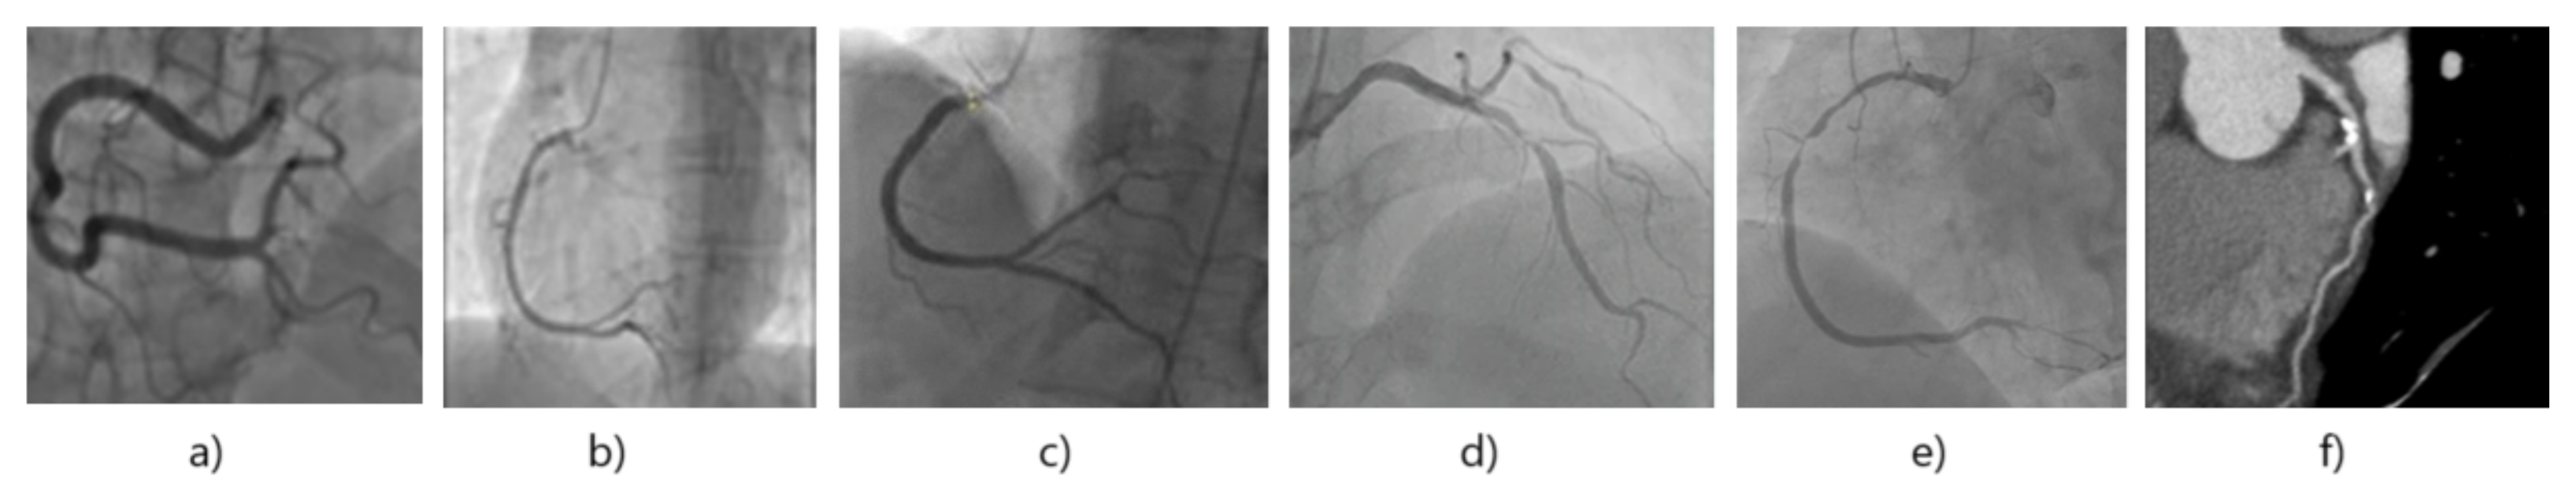

3.1. Dataset

3.1.1. Dataset Composition